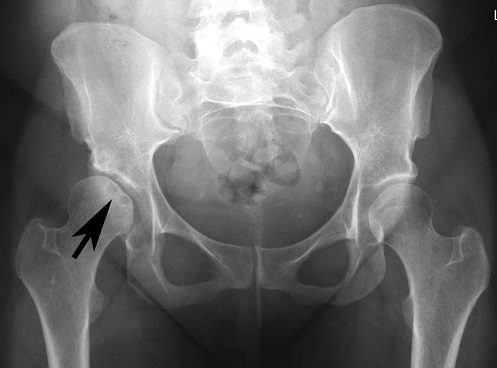

Với công nghệ chỉnh hình trước đây, các bác sĩ thường lên kế hoạch điều trị dựa trên phim X Quang 2D.

Những hình ảnh trên phim X quang không thể hiện rõ các góc khuất, dị tật của xương, đồng thời khó lên kế hoạch phẫu thuật chính xác.

Mô hình in 3D xương của bệnh nhân với độ chính xác gần như tuyệt đối giúp bác sĩ lên kế hoạch phẫu thuật, đo đạc, chuẩn bị xương, dụng cụ để cấy ghép.

Bác sĩ cũng có thể thao tác trên mô hình xương 3D trước khi phẫu thuật thực sự, đảm bảo độ chính xác cao, giảm thời gian phẫu thuật và giảm xâm lấn.